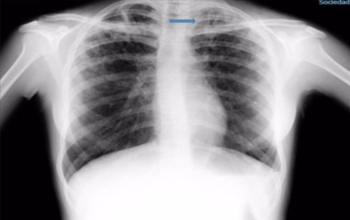

Radiografía de tórax: aumento de la trama intersticial bilateral con lesión tipo caverna en vértice izquierdo (Figura 2).

Figura 2: Radiografía de tórax. Aumento de la trama intersticial bilateral. Flecha azul: lesión tipo caverna en vértice izquierdo.